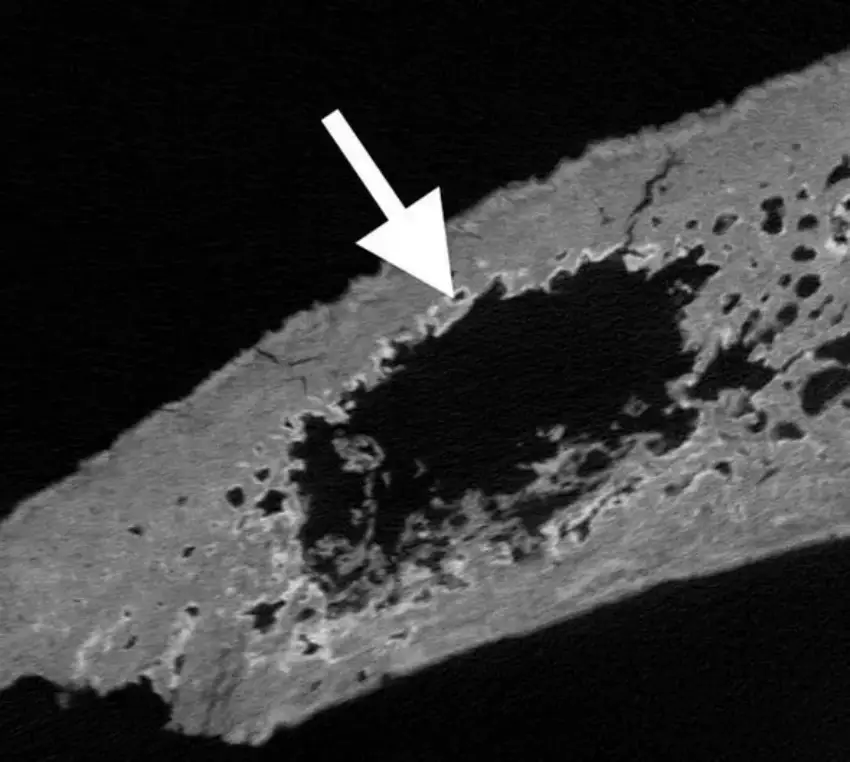

“Only some cases spread to bone, and of these, only a few are visible on the surface, so we looked inside the bone for internal signs.”

Dr. Jenna Dittmar, the study’s co-author, said: “Using CT scans, we were able to identify internal lesions hidden inside bones that appeared normal externally.